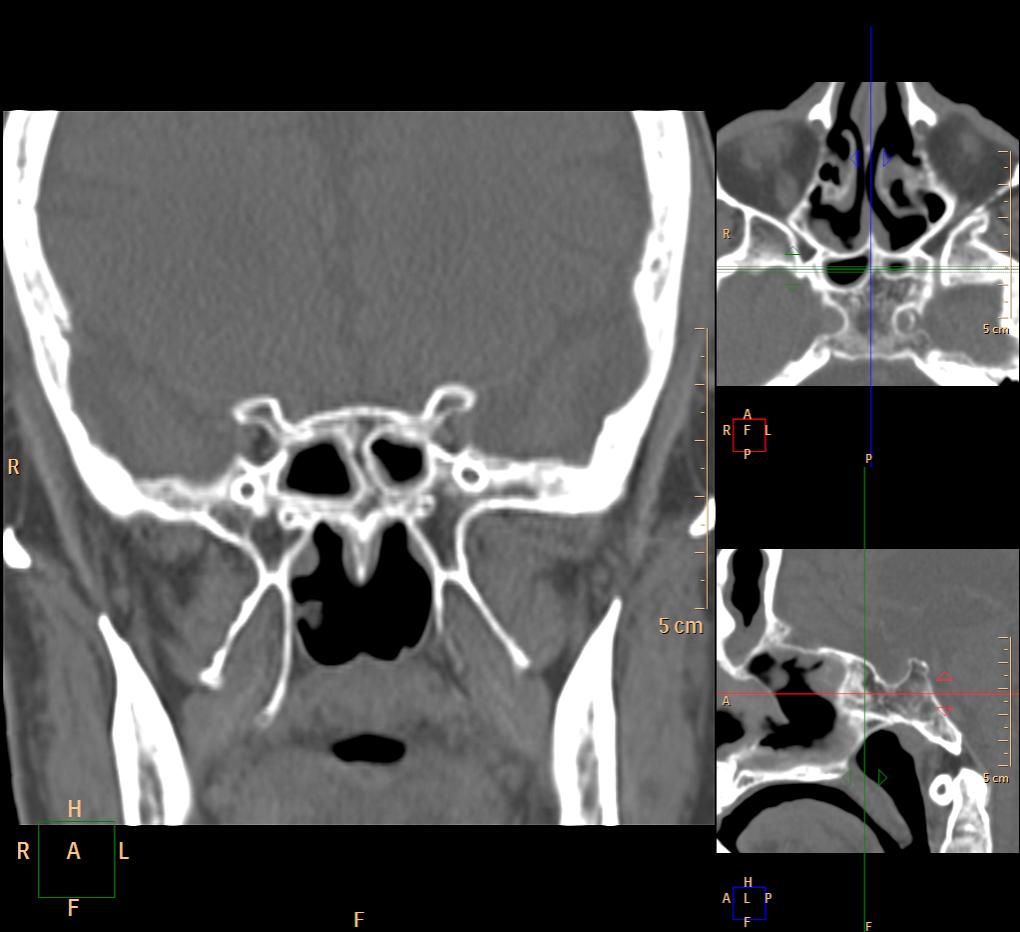

КТ. Разнообразие клиновидной пазухи.

Классическое разделение на 2 половины встречается часто, но еще чаще - несимметричное разделение пазухи.

Вроде основных две, но разнообразные перегородки делят их на бОльшее количество:

Тут, например, 7 камер у одной пациентки: